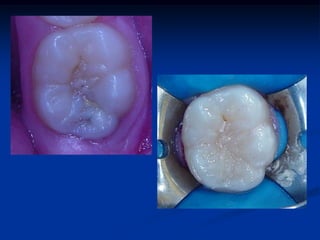

Caso 1- Clínica UNINOVE

1

2

Modus Operandi

3

4

5       6   7

8           9

TÉCNICA DA MOLDAGEMOCLUSAL É uma técnica restauradora que visa reabilitar o mais próximo ao natural a anatomia oclusal e-ou ocluso-proximal, através da confecção de uma matriz ou moldagem oclusal. Objetivos Minimizar as fases de acabamento Reabilitar a anatomia natural

1 2 Modus Operandi

5 6 7 8 9